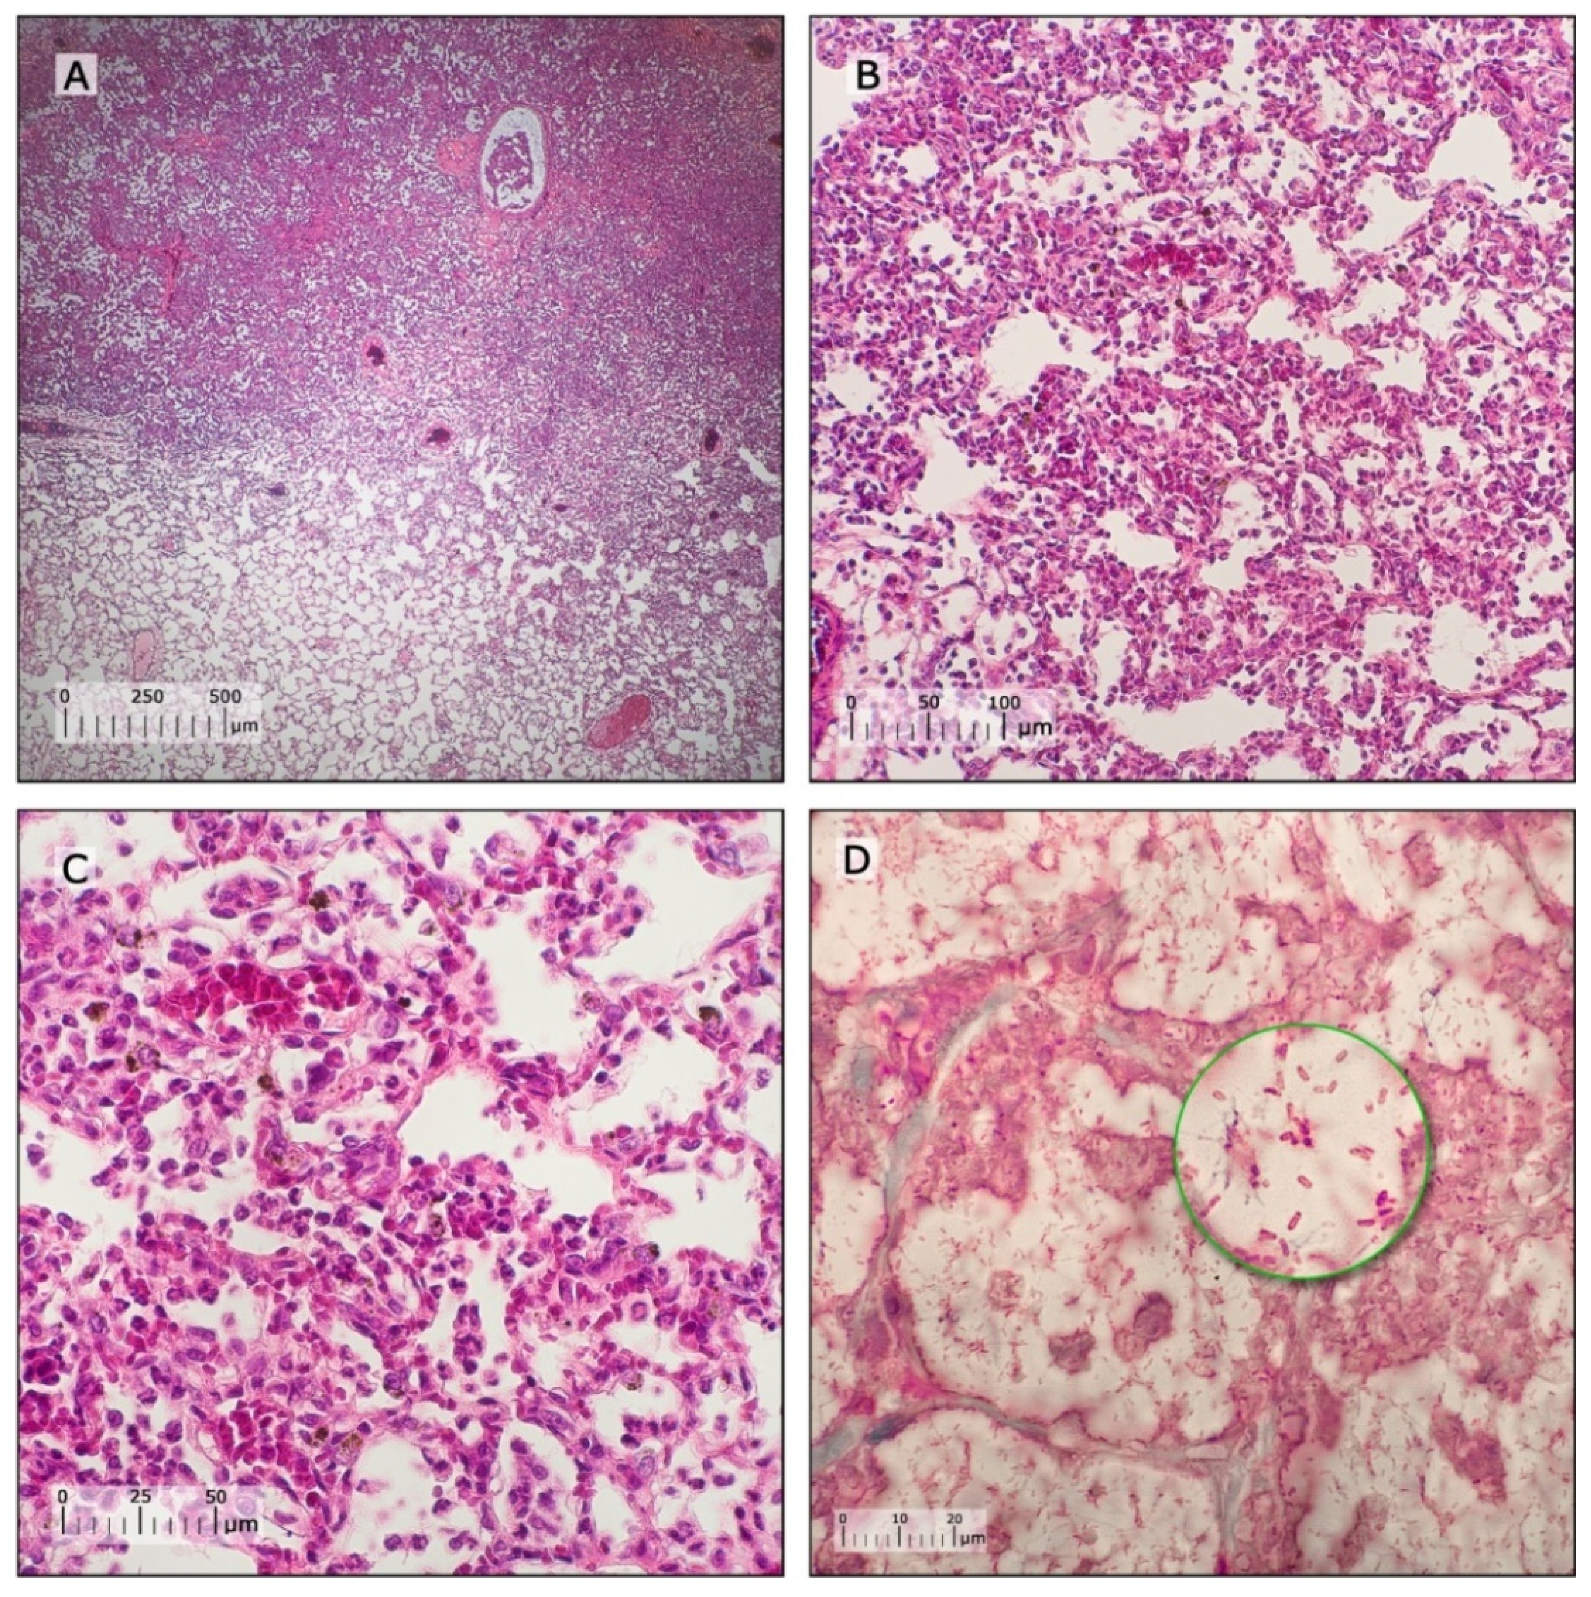

3.4. Characterization of Pneumonia–Septicemia Model